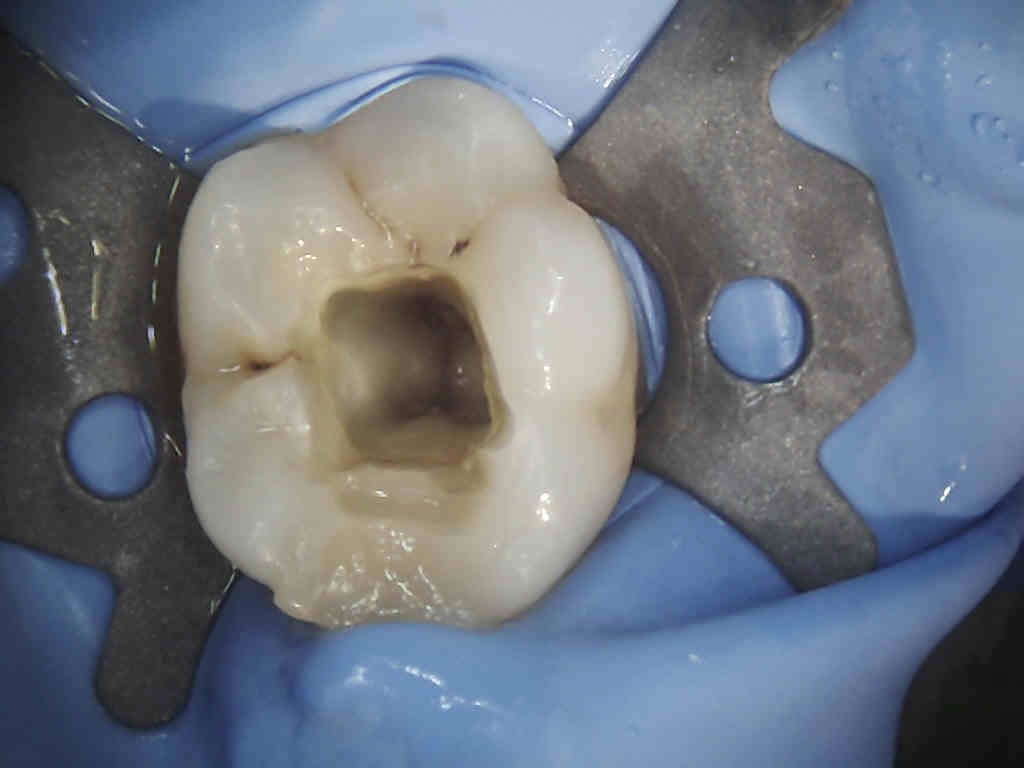

Monto la diga…

Inizio la cavità…

Mentre scendo la ragazza non fa una piega…

Sensazione di sfondamento camera…

Guardo subito con lo specchietto…vuoto e senza sanguinamento…

“Ok, credo che abbiamo azzeccato la diagnosi…finiamo l’apertura per conferma…”

“Ok, credo che abbiamo azzeccato la diagnosi…finiamo l’apertura per conferma…”

Ed ecco qua cosa ho trovato…

“A questo punto le possibilità che il dolore venisse da questo dente sono salite al 95%, fatta salva l’eventuale sindrome da impatto di cibo tra i molari superiori, ma comunque il dente sarebbe stato da devitalizzare e abbiamo scongiurato la comparsa di un ascesso dopo che il male attuale fosse miracolosamente sparito…quindi abbiamo fatto un lavoro utile e probabilmente risolutivo”.

“A questo punto le possibilità che il dolore venisse da questo dente sono salite al 95%, fatta salva l’eventuale sindrome da impatto di cibo tra i molari superiori, ma comunque il dente sarebbe stato da devitalizzare e abbiamo scongiurato la comparsa di un ascesso dopo che il male attuale fosse miracolosamente sparito…quindi abbiamo fatto un lavoro utile e probabilmente risolutivo”.

Lascio ipoclorito due minuti nella camera pulpare…e il risultato è questo…